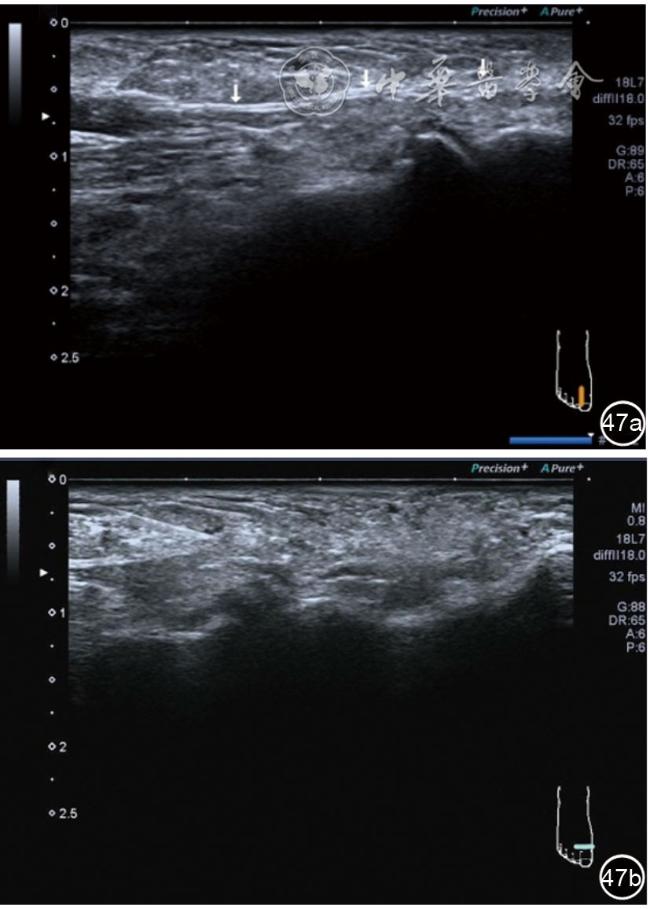

4.腓总神经分支卡压的治疗。常见腓浅神经、腓深神经感觉支卡压。主要表现为足背侧的感觉减退。腓深神经只支配第一、二足趾之间的感觉,腓浅神经支配的感觉区域较多,第一、二足趾之间外的足背感觉均由腓浅神经支配,根据感觉障碍区域确定卡压神经,超声可以明确卡压部位和原因。超声可显示卡压神经增粗,回声减低,局部软组织回声不均匀等(图4445)。治疗以液压松解药物注射为主。以腓深神经为例进行介绍。常见卡压部位在小腿和足背部。根据卡压部位不同,患者采取不同的体位。如果在小腿部采用平卧位,膝关节伸直位即可。穿刺区域常规消毒,探头涂抹耦合剂后套入无菌手套碘伏消毒或使用无菌耦合剂。将探头置于患者皮肤表面,小腿部位采用短轴扫查,确定神经卡压最明显的部位后,用一次性5 ml注射器,应用25G注射针头抽吸0.5%利多卡因4 ml+地塞米松3 mg平面内进针到达神经周围,注意回抽无血液回流后进行注射(图46),完成注射松解,拔出针头,局部压迫3分钟,创可贴覆盖。如果在足背部可以采取平卧位,屈髋、屈膝将足平放于治疗床面。治疗前准备同小腿部,采用长轴显示神经,确定神经卡压最明显的部位后,用一次性5 ml注射器,应用25G注射针头抽吸0.5%利多卡因2 ml+地塞米松1 mg平面内进针到达神经表面进行注射(图47),完成注射松解,拔出针头,局部压迫3分钟,创可贴覆盖。

图47 腓深神经足背处卡压及穿刺注射治疗超声图像